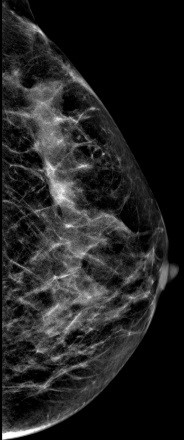

V-preview图像: